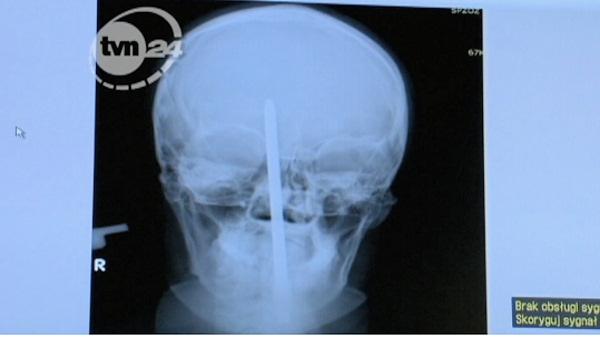

1 of 10: A man from Poland has become a walking medical miracle. These are X-Rays of the 25-year-old patient, who had a screwdriver lodged about two inches into his head. The man told doctors it happened when he fell down, but he doesn't remember much else, because he lost consciousness. Doctors successfully removed the tool during a three-hour surgery. The screwdriver did not damage the man's eyes or his brain.